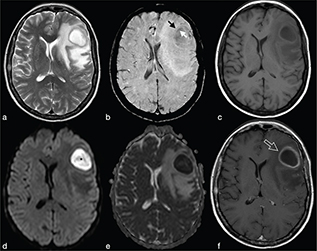

Fungal BA are rare and usually demonstrate low T2w signal in the centre and a ring-enhanced wall. Restricted diffusion may be seen in the capsule of the fungal abscess called “intracavitary projections.” Low ADC values are due to fungal organisms located at the periphery of the lesions and mucoid material.7 Opposite to pyogenic BA, fungal BA do not have the “dual rim” sign on SWI images but are characterised by a thick dark peripheral rim with multiple intralesional dark spots related to intralesional haemorrhage, typical in Aspergillus infection (Figure 15). Moreover, MRS may show lipid, lactate, amino acids and trehalose (3.6–8 ppm).15 In particular, trehalose has been observed in cryptococcosis.7

FIG 15. Fungal Brain Abscess (Aspergillus) in an Immunocompromised 44-Year-Old Man with Headache and Progressive Deterioration of Consciousness for 4 Days. A right parietal mass was observed in close proximity to the superior sagittal sinus with perifocal vasogenic oedema on T2w. (b, c) Spontaneous T1 shortening likely caused by xanthochromic fluid (extracellular methemoglobin) is present (b) with slight irregular enhancement after i.v. Gd administration (c). In fungal abscess, the rim of irregular hypointense signal on SWI, rather than haemoglobin breakdown products, may be consistent with the presence of elements with paramagnetic properties, such as iron or magnesium (d). DWI (e) and ADC maps (f) reveal heterogeneous signal with restricted diffusion in the lesional core and in the peripheral rim.

Cerebral toxoplasmosis is typical of immunocompromised patients. MRI shows multiple lesions in different stages of evolution typically located in the subcortical and periventricular white matter, in the basal ganglia and thalami. In particular, two signs are recognised as typical of toxoplasmosis: the “concentric” target sign (concentric alternating hypointense and hyperintense rims in T2w images), and the “eccentric” target sign (peripheral rim of enhancement and focal lateral eccentric enhancing nodule on T1w post-contrast) (Figure 16). On DWI, the centre of the toxoplasma abscess is seen to have ADC values higher than in pyogenic abscesses.22

FIG 16. Multiple Toxoplasma gondii Abscesses in a 45-Year-Old Immunocompromised Woman. T2w (a), T1+Gd (b, f), rCBV map (c), DWI (d) and ADC map (e). Multiple supratentorial brain abscesses in various stages of development with enhancing asymmetric nodules after Gd-injection (“eccentric target sign”) (arrows) can be observed (b, f). Note also the concentric alternating zones of hypo- and hyperintensities on T2w: “concentric target sign” (circle in a). Toxoplasma gondii abscesses typically do not show a core of restricted diffusion on DWI (asterisk in d) while low ADC values may be seen in the capsule (e).